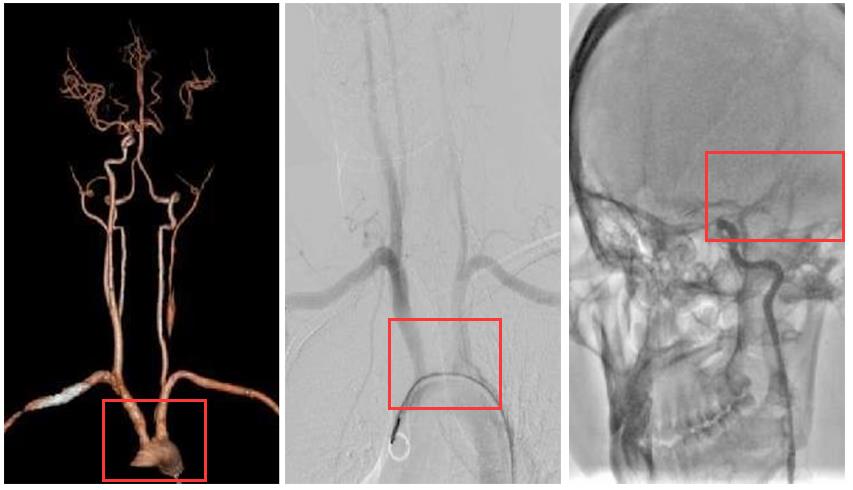

小云被送到中大五院后,医院立即启动脑卒中绿色通道,检查提示患者左侧颈总动脉起始段明显狭窄,中远段大部分闭塞;左侧颈内动脉颈段闭塞;左侧大脑中动脉M1段、M2段近侧闭塞,被诊断为急性脑梗死。

小云被送到中大五院后,医院立即启动脑卒中绿色通道,检查提示患者左侧颈总动脉起始段明显狭窄,中远段大部分闭塞;左侧颈内动脉颈段闭塞;左侧大脑中动脉M1段、M2段近侧闭塞,被诊断为急性脑梗死。